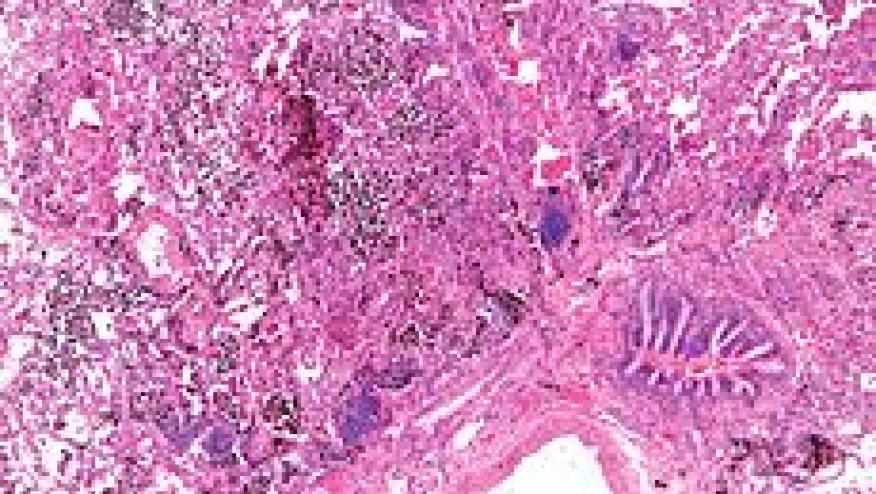

Diffuse alveolar hemorrhage (DAH) is a rare but catastrophic complication of systemic lupus erythematosus. Presentations are usually acute and the potential for significant morbidity and mortality risk mandates early diagnosis and aggressive interventions.